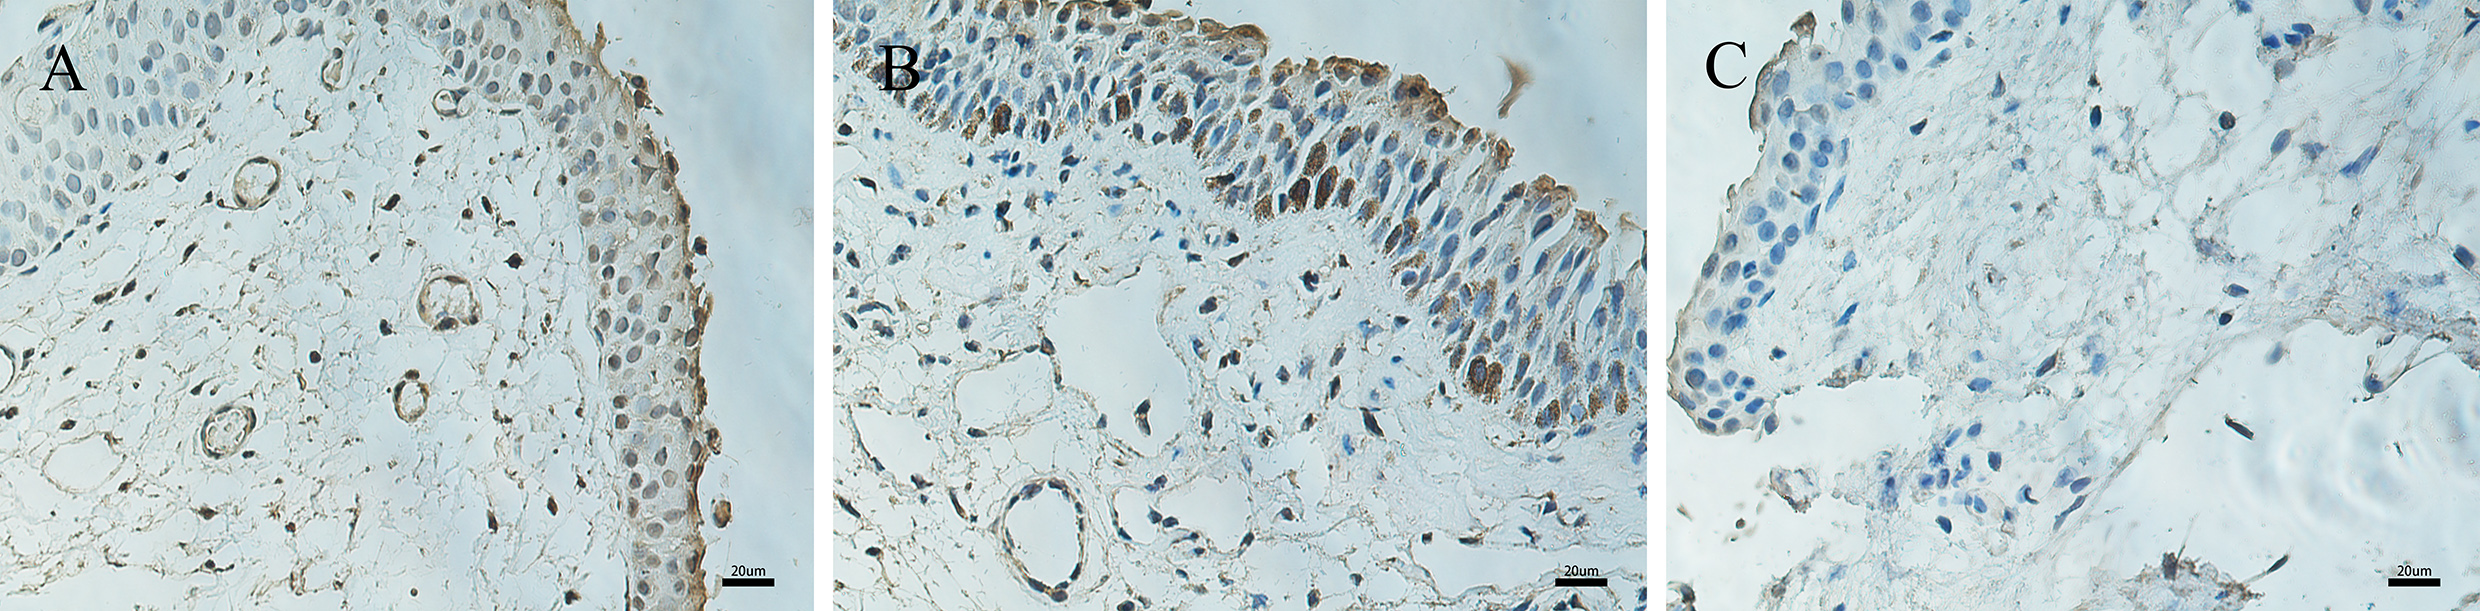

Figure 3. Immunohistochemical expression of VEGF in pterygium and normal conjunctiva. Immunohistochemical expression of VEGF in pterygium

(A–B) and normal conjunctiva (C). A: Epithelial and stromal layers display moderate VEGF immunoreactivity. B: There is moderate to strong nuclear immunoreactivity in the basal layers of epithelial cells. C: There is almost no positive expression in control conjunctival tissue (400X, bar = 20 μm).